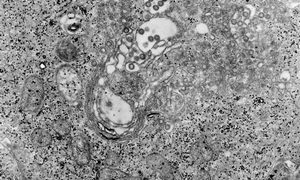

クリプトスポリジウム症は、クリプトスポリジウム原虫(主にクリプトスポリジウム・パルバム:C.parvum)の感染によって引き起こされる重要な人獣共通感染性の腸管感染症です。C.andersoni(クリプトスポリジウム・アンダーソニ)、C.b...